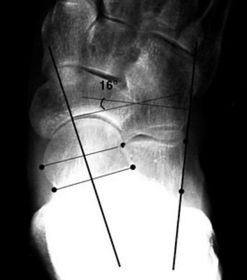

What angle is this? Is this normal or abnormal? | 1st intermetatarsal angle Abnormal. Greater than 9 degrees is abnormal. Usually due to metatarsus primus varus |